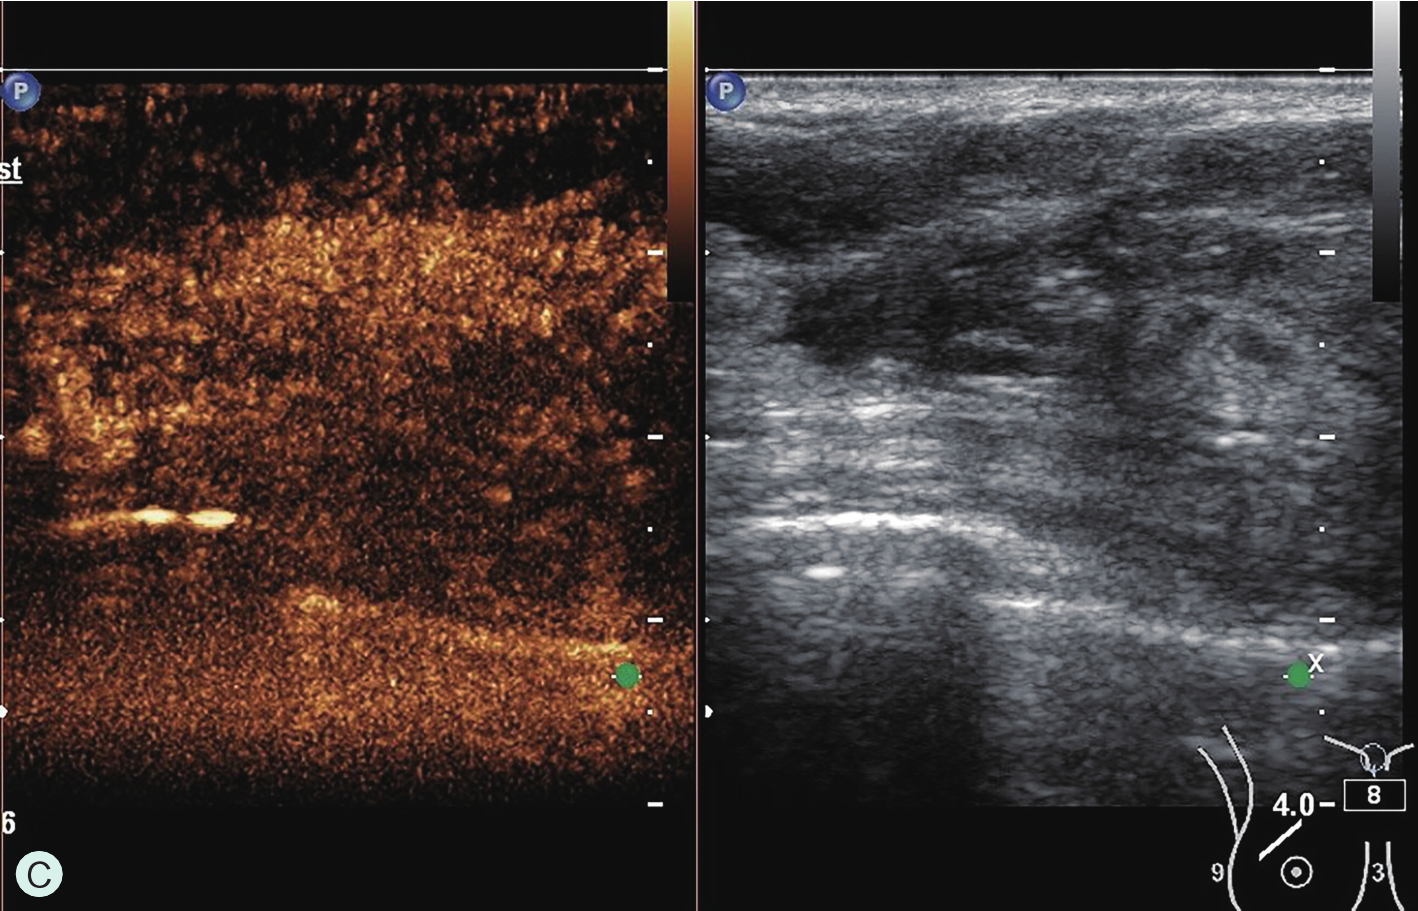

所有具有超声造影功能并支持浅表线阵探头造影的超声诊断仪器均可用于乳腺超声造影检查。由于乳腺超声造影对设备的造影效果、探头选择及参数调节要求很高,故在开展乳腺超声造影前,必须充分论证其造影效果,与设备应用专员共同调节造影参数至乳腺超声造影最佳模式。常规高频线阵探头不能用于乳腺超声造影,而必须选用低频线阵探头。下面将根据笔者所在单位临床工作实际,列举几种超声仪器的乳腺超声造影参数及所用探头供读者参考(图2-1-3~图2-1-7)。

图2-1-3 GE Logic E9乳腺超声造影参数及所用探头

A.GE Logic E9乳腺超声造影参数;B.GE Logic E9乳腺超声造影探头9L